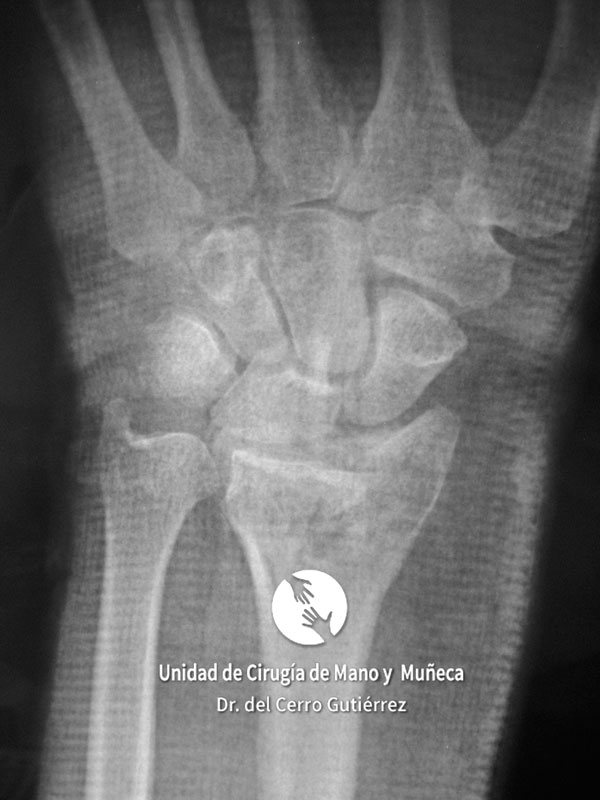

Imágenes de diagnótico de fracturas del radio distal de la muñeca

Las imágenes de diagnóstico son fundamentales para evaluar las fracturas del radio distal, identificar su gravedad y definir el tratamiento más adecuado. A continuación, presentamos una serie de ejemplos que muestran diferentes tipos de fracturas.

Fractura del Radio. Avulsión Estiloides.